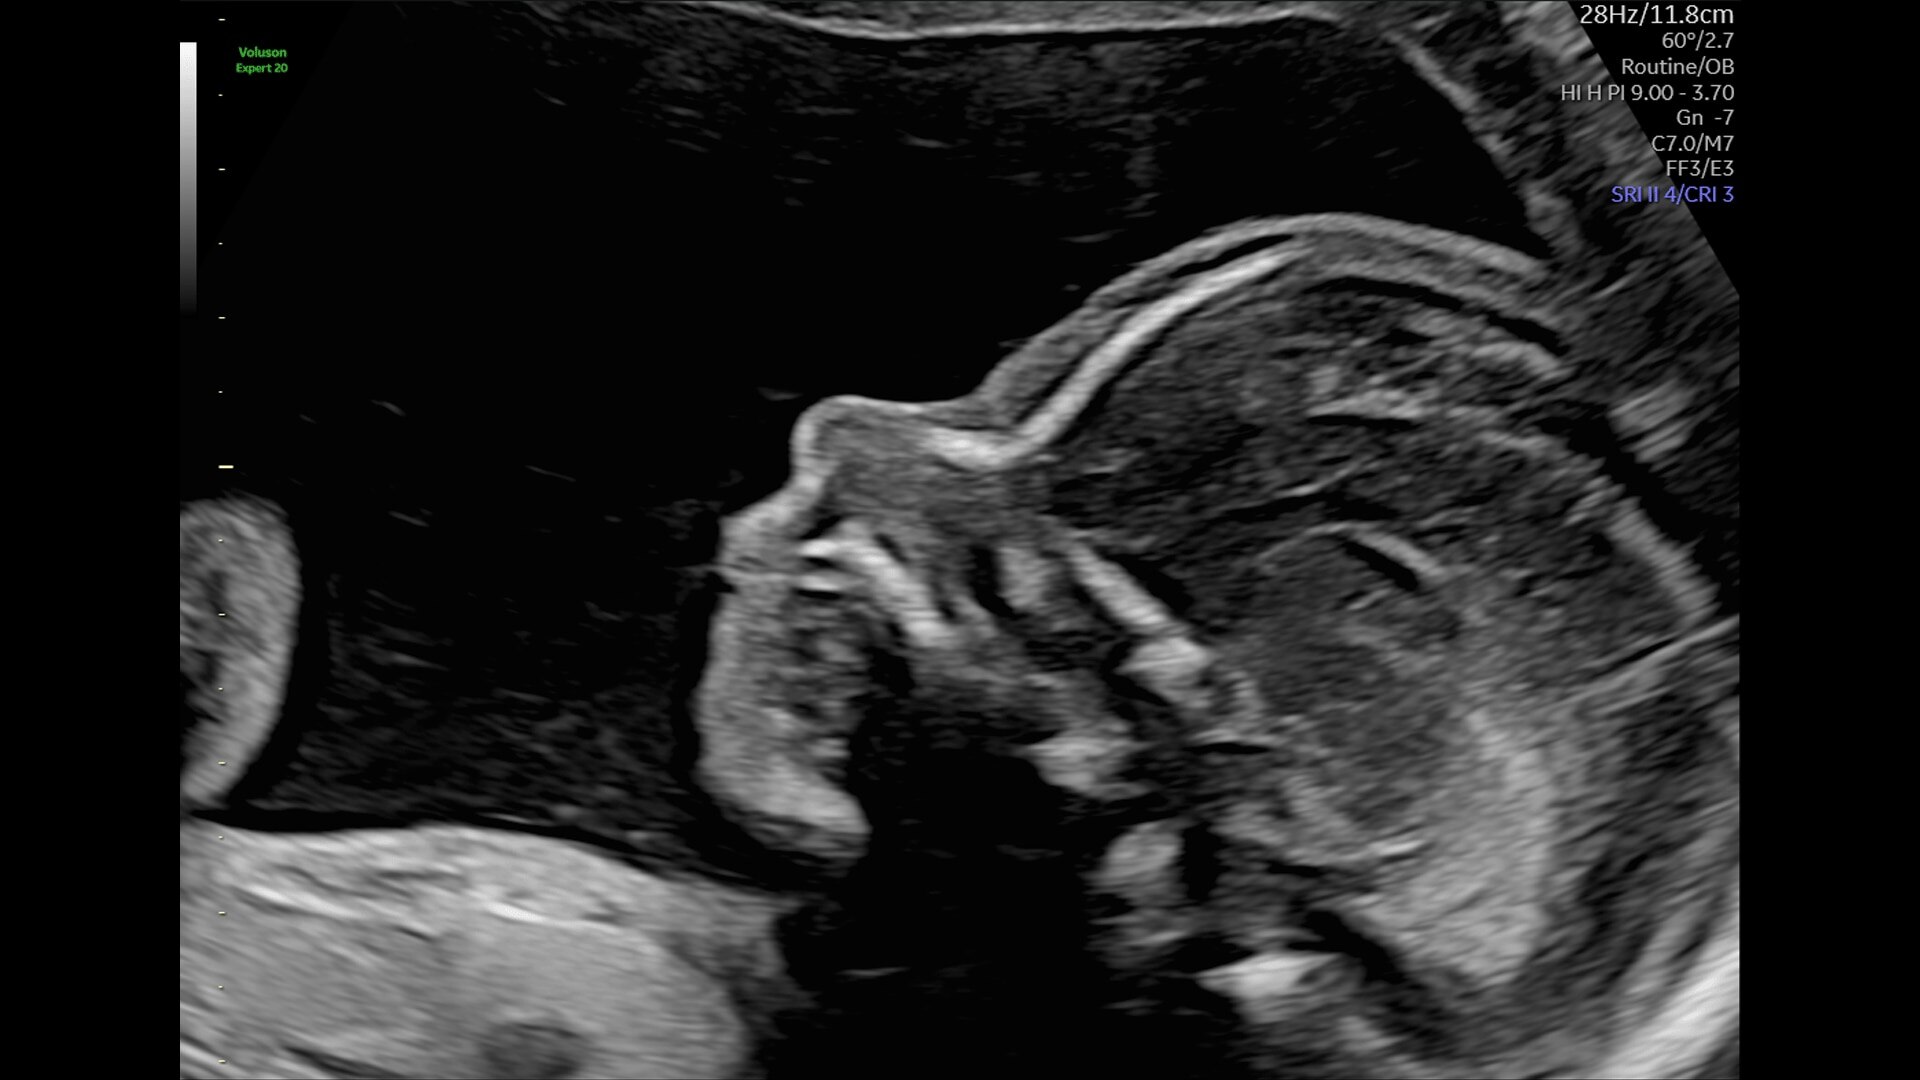

Generate spectacular 2D/3D and color Doppler images with increased penetration and stunning clarity, to help visualize critical details needed for diagnostic assurance. The Lyric Architecture unlocks new imaging and processing power to expand your imaging capabilities for years to come